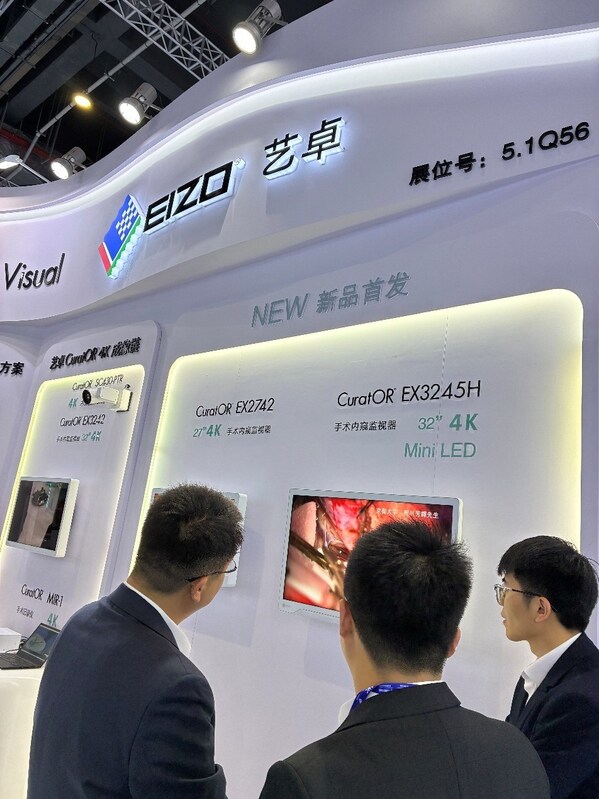

本届展会,艺卓精心特意打造了模块化的展示空间,特设"新品首发""艺卓放射影像显示解决方案"、"艺卓内窥影像显示解决方案",以及"艺卓CuratOR4K成像链"等多个专区,覆盖了诊断、手术、临床监护等全场景应用。

在新品首发专区,艺卓展示了首款Mini‑LED 4K 2D医用监视器EX3245H,这也是该产品的全球首展。EX3245H拥有32英寸4K超高清宽屏,采用高密度、全阵列Mini‑LED背光,实现了1900cd/m²峰值亮度与1000000:1超高对比度,2000 多个局部调光区结合EIZO专属算法,可精准呈现精细的血管与组织结构。同时,其采用光学贴合工艺减少了环境反射,贴合后的屏幕还能有效地减少画面泛白,产生更深的黑色,确保在手术室强光下依然清晰可视,适配内窥镜、显微手术及机器人辅助手术等高精度临床场景,为精准手术提供可靠视觉保障。

4K 2D手术监视器EX2742是艺卓带来的另外一款国内首展产品,适用于内窥镜检查、显微手术及其他高精度手术。EX2742具有27英寸显示器、4K UHD分辨率、BT.2020色域、820cd/㎡高亮度与2000:1高对比度,光学贴合技术可有效减少屏幕反射,兼容HDR使支持 HDR的内窥镜摄像机拍摄的影像更加逼真。前面板的全平面防护玻璃易于清洁,监视器正面的防尘防水等级为 IP45,整机防尘防水等级为IP32,适配手术室严苛环境。搭配画中画、画边画功能与信号丢失自动切换保护机制,为临床手术提供安全稳定的显示保障。